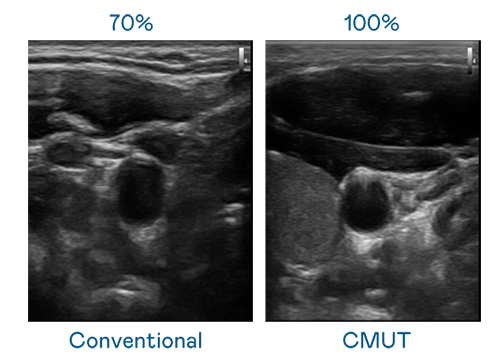

CMUT 技术是一种用电容式微机电元件来产生超音波讯号的技术。与传统 PZT 压电式技术相比,CMUT 频宽增加 30%,更宽频的超音波讯号让影像解析度大幅提升,是实现高影像品质医疗超音波扫描、促进精准医疗发展的关键技术。

超音波影像的解析度高低,首先取决于探头能发出的讯号频宽。888电子 CMUT 可提供高清晰的超音波讯号,提供高频宽、高灵敏度、影像纹理细节更高的超音波影像,协助医护人员缩短影像判读时间及利用精准的医疗影像进行诊断。